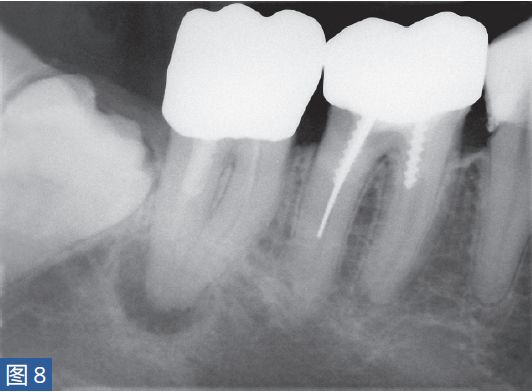

急性根尖周脓肿(AAA acute apical abscess)急性根尖脓肿(图8 和9)是一种局部的或者弥漫性的液性病变。由坏死牙髓产生的微生物和非微生物刺激所引起的严重炎症反应造成了根尖周组织的破坏。患者通常表现出中度至重度疼痛,根据严重程度还可能出现发热和白细胞增多的全身症状。临床诊断显示牙髓电活力测试结果阴性。叩诊和触诊通常会引起疼痛。如果脓肿仅限于骨内,则不出现肿胀症状。放射学检查,根尖周组织表现从无变化到发生明显变化。

图8:47 牙齿AAA。术前X 线片。患者就诊时有发烧症状,且叩诊和触诊疼痛明显。